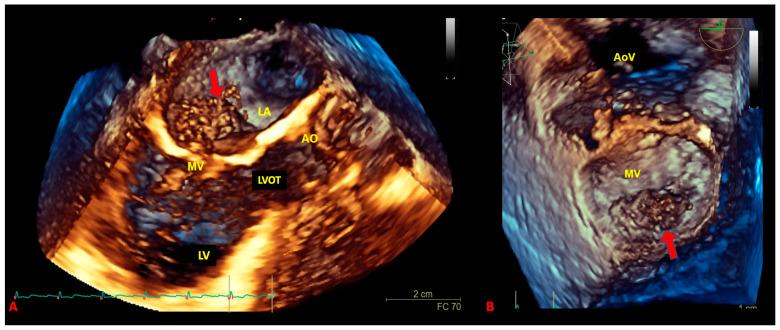

Primary malignant cardiac tumors are rare, with a prevalence of about 0.01% among all cancer histotypes. At least 60% of them are primary soft tissue sarcomas of the heart (pSTS-h) that represent almost 1% of all STSs. The cardiac site of origin is the best way to classify pSTS-h as it is directly linked to the surgical approach for cancer removal. Indeed, histological differentiation should integrate the classification to provide insights into prognosis and survival expectancy of the patients. The prognosis of pSTS-h is severe and mostly influenced by the primary localization of the tumor, the difficulty in achieving complete surgical and pharmacological eradication, and the aggressive biological features of malignant cells. This review aims to provide a detailed literature overview of the most relevant issues on primary soft tissue sarcoma of the heart and highlight potential diagnostic and therapeutic future perspectives.